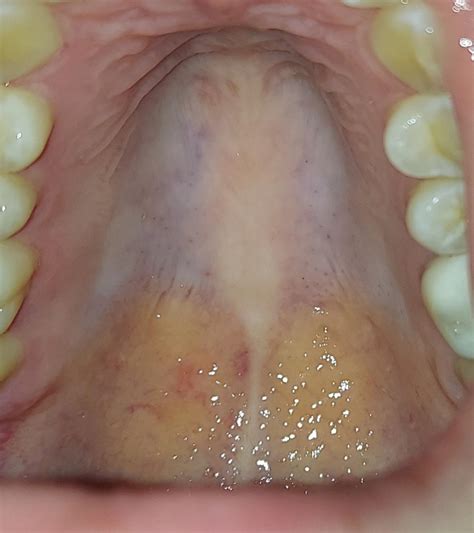

Understanding the Palate

The palate, also known as the roof of the mouth, is a crucial part of the oral cavity. It is divided into two main parts: the hard palate and the soft palate. The hard palate is the bony front portion, while the soft palate is the muscular back portion that includes the uvula. The palate plays a vital role in speech, swallowing, and breathing. When your palate is itchy, it can disrupt these functions and cause significant discomfort.

• Oral Thrush: This is a yeast infection that can cause white patches and an itchy feeling in the mouth. It is more common in people with weakened immune systems.